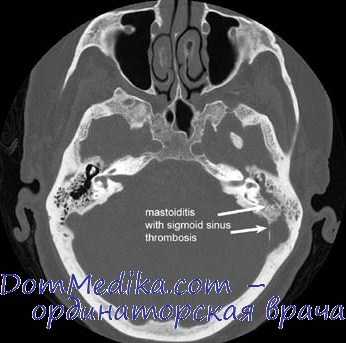

КТ при мастоидите с тромбозом сигмовидного синуса

Распространение гнойного воспаления в самом сосцевидном отростке происходит по наиболее пневматизированным ячейкам, что обуславливает разнообразие возникающих при мастоидите осложнений и их зависимость от строения сосцевидного отростка. Воспаление перисинуозной группы ячеек приводит к поражению сигмовидного синуса с развитием флебита и тромбофлебита. Гнойное разрушение перифациальных ячеек сопровождается невритом лицевого нерва, перилабиринтных — гнойным лабиринтитом. Верхушечные мастоидиты осложняются затеканием гноя в межфасциальные пространства шеи, в результате чего гноеродные микроорганизмы могут проникнуть в средостение и вызвать появление гнойного медиастинита.